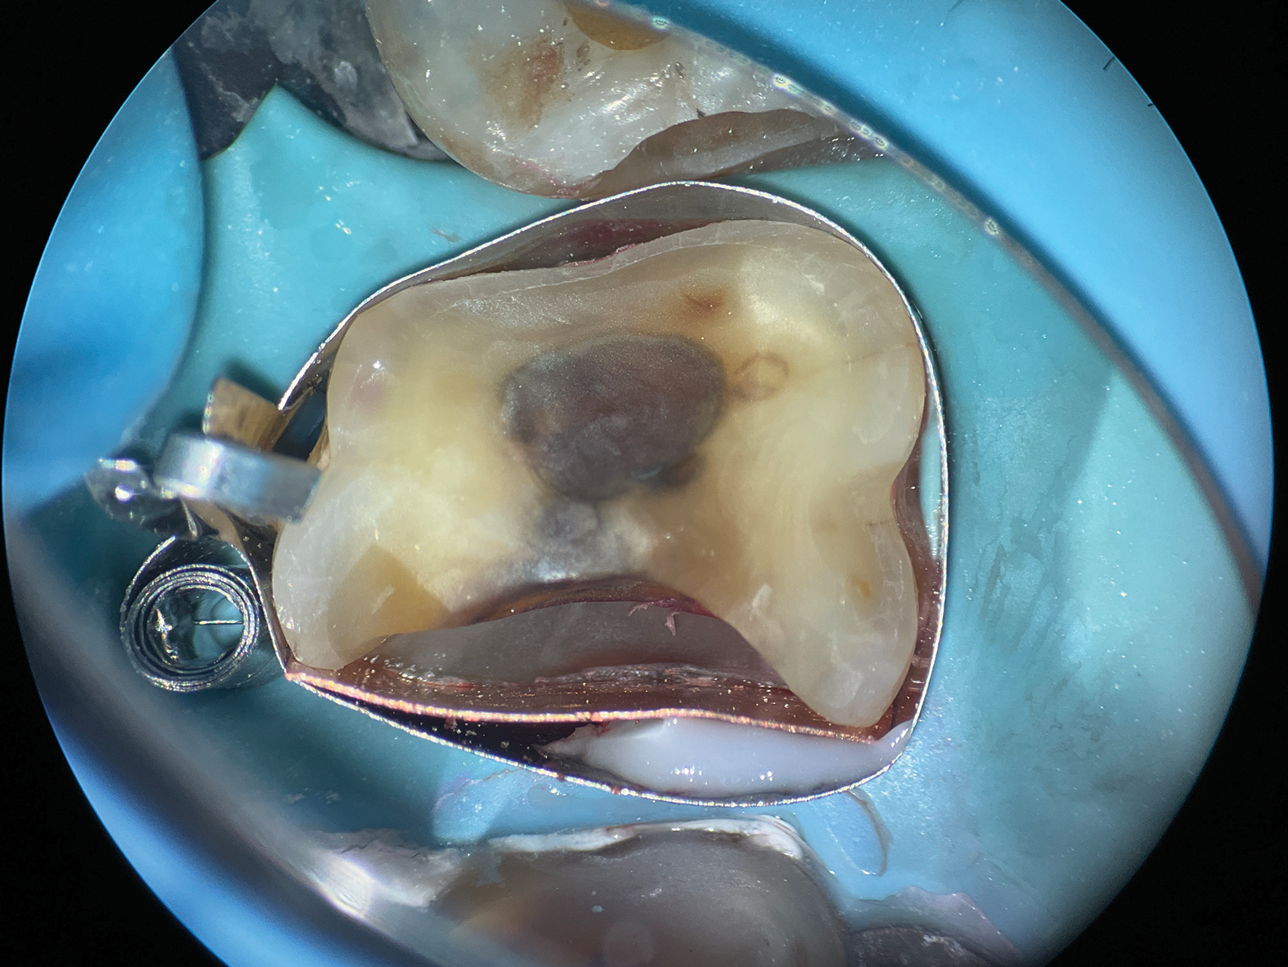

In cases involving extremely deep defects that extend to the bone level, achieving an adequate seal and proper isolation for adhesive procedures can be particularly challenging (Figure 10 and Figure 11). Oftentimes, a single matrix proves insufficient to reach the depth of such defects and effectively shield the cavity from contamination by saliva or blood (Figure 12).

The matrix-in-matrix technique provides a practical and effective solution for these cases (Figure 13). By introducing a second matrix within the first, more specifically, a copper band that has been carefully cut and positioned inside a conventional matrix, the seal is significantly enhanced. This dual-layered approach not only extends the matrix coverage to the full depth of the defect for isolation but also ensures stability in the critical treatment area.

(10.) A close-up distolingual view of a mandibular molar after the removal of caries that extended to the bone level.

Figure 10

(11.) A Willems probe was used to determine that the depth of the margin was approximately 7 mm from the occlusal surface.

Figure 11

(12.) After subgingival placement of a Tofflemire matrix, despite using a wedge and adding additional support with polytetrafluoroethylene tape, fluid infiltration persists through the matrix and margin.

Figure 12

(13.) A wide 2-mil copper band was placed as an additional matrix to create absolute isolation, effectively sealing the space between the Tofflemire matrix and the margin.

Figure 13